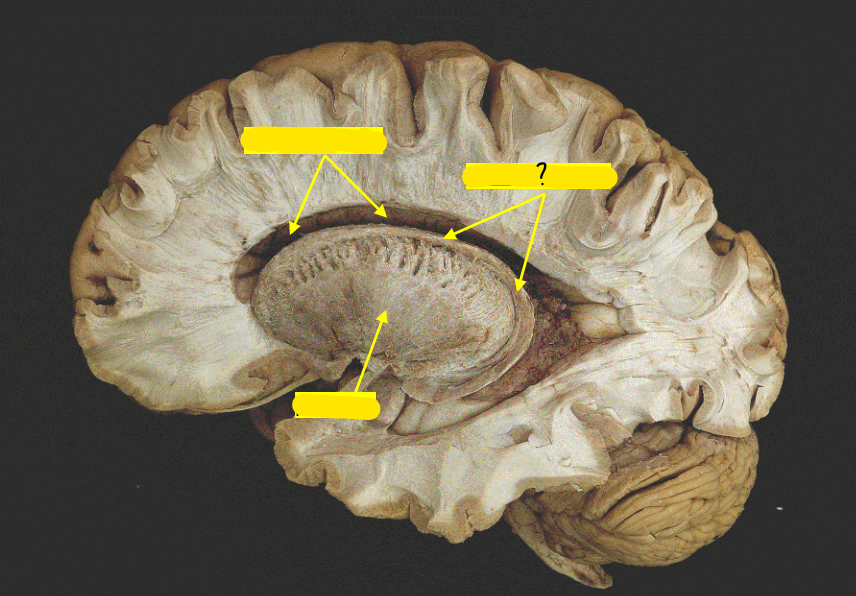

caudate nucleus

putamen

globus pallidus